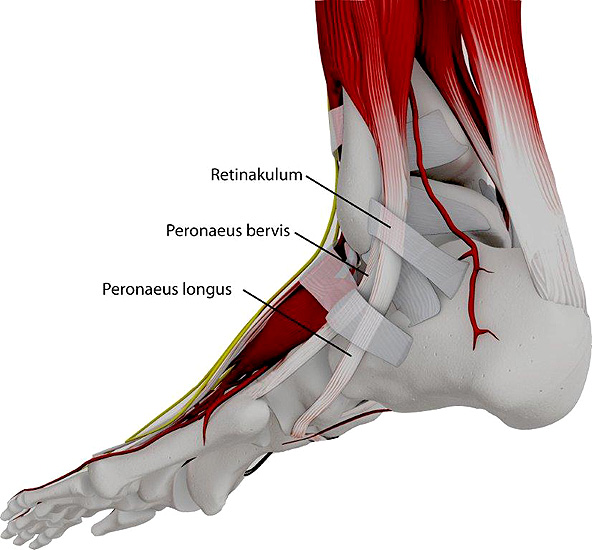

Die Peroneus brevis und die Peroneus longus Sehne verlaufen normalerweise hinter der Fibula (Abbildung 1). Neben der Gleitrinne an der Fibularückfläche sorgt das Retinaculum peroneale und das Retinaculum extensorum für eine weitere Stabilisierung. Bei der Peronealsehnenluxation oder –Instabilität können verschiedene Formen unterschieden werden (Abbildung 2):

Etwa ein Drittel der Sehnenluxationen entsteht jedoch idiopathisch ohne adäquates Trauma. Als Ursache wird hier neben einer Schwäche des Retinaculums eine unzureichende Tiefe der Sehnenrinne an der hinteren Gelenkfläche der Fibulaspitze mit flacher Randleiste angenommen 567.